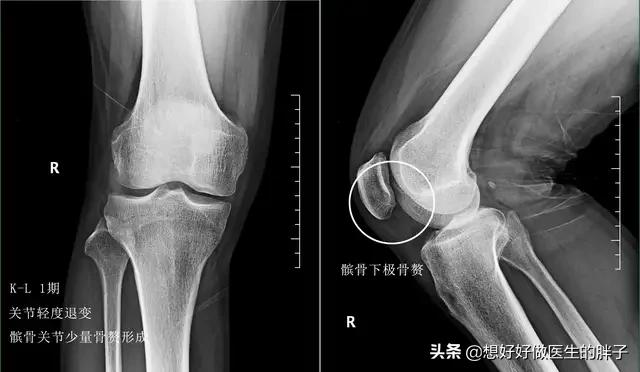

我们身体上所谓的骨刺,医学上称之为骨赘,也叫骨质增生,发生在关节的骨质增生,主要的原因是由于关节的稳定性出现了异常,而产生骨质增生的基础是由于关节软骨的磨损。

所以从理论上来讲,骨赘是属于帮助我们身体维持稳定性的一种结构,但是当关节软骨进一步的磨损,骨赘会越来越大,就会刺激到周边的软组织、韧带、神经等组织与结构,导致患者出现明显的疼痛,当检查x线的时候会发现这些骨赘形成类似刺状,于是骨刺这个说法就诞生了……!

大部分关节软骨损伤的患者在早期的症状不是特别的重,偶尔表现为上下楼梯的疼痛和屈伸关节的时候有明显的疼痛,此时很多患者去医院进行检查,会发现有轻度的骨质增生,这是由于关节软骨并不是磨损的特别重,所以骨赘不会形成的特别多,此时作为患者应该是以休息为主,减少刺激关节软骨的动作,尽量不要做剧烈的运动来反复刺激关节软骨;可以尝试口服氨糖三个月观察疗效;如果疼痛比较明显的时候可以外用一些抗炎镇痛药帮助控制疼痛;此时可以适当的进行关节周围肌肉力量的强化训练,帮助增加关节的稳定性,也就侧面的减缓了骨赘形成的速度,这种康复锻炼应该贯穿于整个骨赘治疗的全程,是基础治疗。